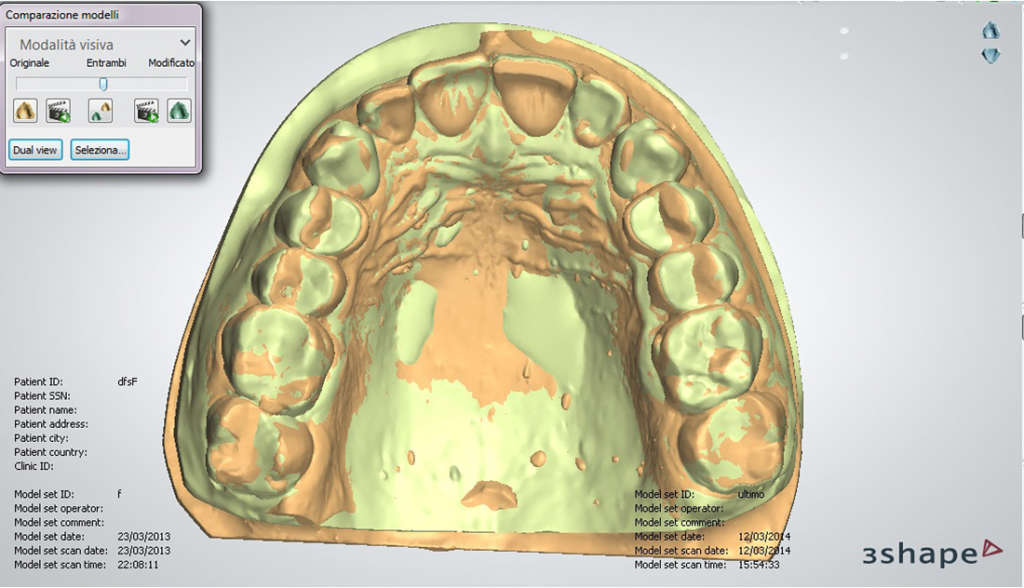

AVVENTO DELLA PROCEDURA CAD/CAM

Con l’avvento della procedura CAD/CAM, l’odontotecnico sottopone il modello in gesso ricavato dalle impronte, alla lettura da parte di uno speciale scanner 3D (tridimensionale) il quale, grazie al software, riproduce in digitale il manufatto.

Da questo momento in poi è possibile apportare le modifiche alla protesi virtuale direttamente con il computer.

Terminata la fase CAD, quella appena descritta, inizia la fase CAM. Una volta conclusa la progettazione da parte del tecnico, il software produce un file digitale che è mandato ad una speciale fresatrice computer assistita che lo elabora e, comincia a fresare/intagliare il blocchetto di materiale che si è scelto per la protesi.